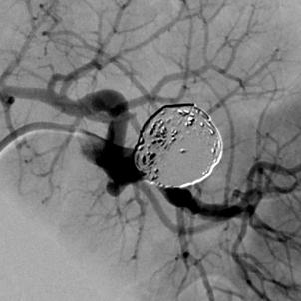

脾动脉远端动脉瘤栓塞 Hilar splenic aneurysm ~ 24 mm Coaxial catheterization / Rebar 18,Concerto detachable coils Coil packing density 28% Patent parent artery / Retained splenic perfusion Hilar splenic aneurysm Coaxial catheterization / R

Hilar splenic aneurysm ~ 24 mm

Coaxial catheterization / Rebar™ 18,Concerto™ detachable coils |

Coil packing density 28% |

Patent parent artery / Retained splenic perfusion